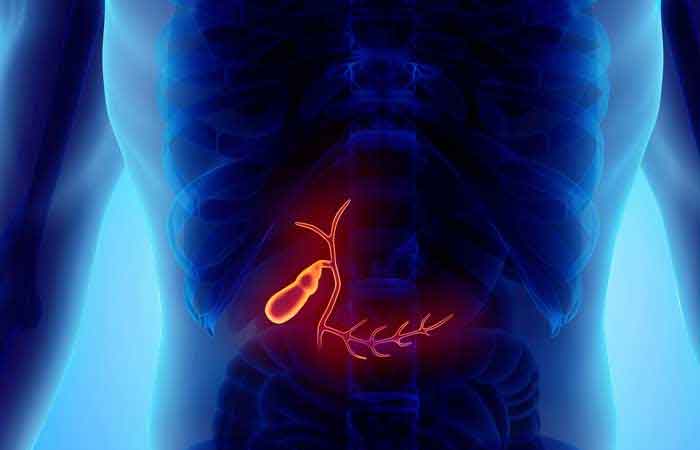

قیمت: 45٬000 تومان - دسته بندی فایل: پاورپوینتپاورپوینت پولیپ کیسه صفرا Gallbladder Polyps

خرید پاورپوینت حرفه ای با موضوع پاورپوینت پولیپ کیسه صفرا Gallbladder Polyps از لوکس فایل